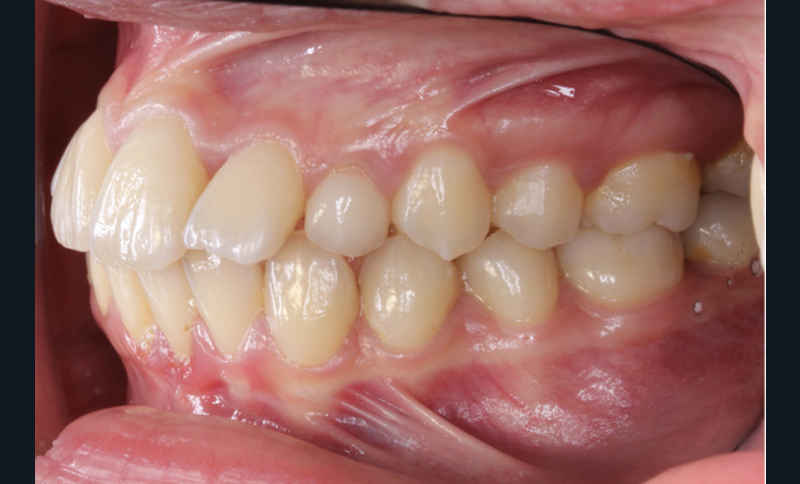

Les examens cliniques et radiologiques ont mis en évidence l’inclusion de 13 et 23, une légère classe II bilatérale par perte d’ancrage, un biotype parodontal de type IV de Maynard et Wilson avec une insertion du frein mandibulaire antérieur papillaire, une biproalvéolie et une typologie hypodivergente. La réalisation d’un examen tridimensionnel a permis de confirmer la localisation palatine de 23 et vestibulaire de 13 ainsi que de visualiser l’étendue des résorptions radiculaires touchant 12, 21 et 22 (fig. 1a-i).

La traction des canines incluses s’est faite sur des sectionnels postérieurs en TMA .017 x .025 de type Ballista (fig. 4a,b). Un décapuchonnage de la 23 a dû être réalisé pour lui permettre de transpercer la muqueuse palatine. Des cales occlusales ont été ajoutées pour assurer le passage de la canine de la situation palatine à vestibulaire. Un contrôle radiologique a permis de suivre la traction. Parallèlement, la fermeture des espaces mandibulaires s’est faite par perte d’ancrage postérieure et par redressement antérieur grâce à des chaînettes élastomériques.

Les caches esthétiques ont été progressivement diminués jusqu’à leur suppression complète. Une fois l’alignement des canines obtenu, la prise en charge de 11 et 21 sur un NiTi .014 a débuté. Des forces très douces avec un contrôle radiologique tous les trois mois ont ensuite permis l’alignement et la fermeture des derniers espaces maxillaires. Une coronoplastie soustractive de 13 et 23 a été réalisée pour les transformer en 12 et 22. La vitalité de 11 et 21 a été conservée. En contention, deux fils collés ont été mis en place (13-23 et 33-43) ainsi qu’une gouttière thermoformée maxillaire amovible à port nocturne. Le traitement a duré vingt-neuf mois (fig. 5a-f).